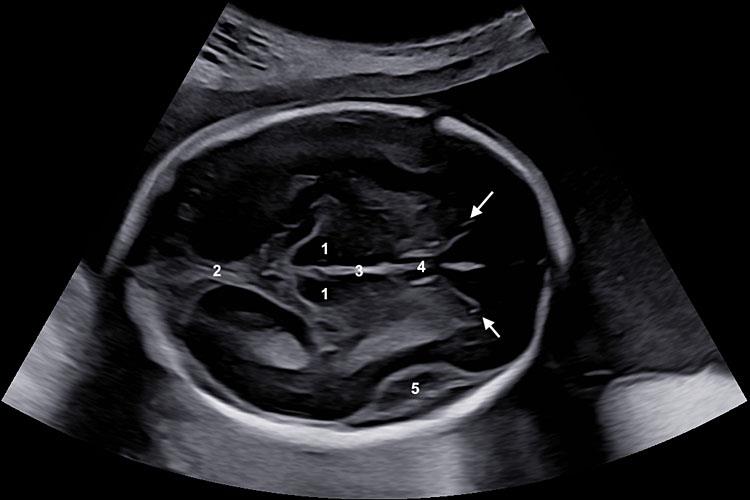

The measurement of OFD is typically done during an ultrasound scan. The sonographer measures the distance between the outer edge of the occipital bone to the outer edge of the frontal bone on an axial plane of the fetal head. This is done using specialized ultrasound equipment, and the accuracy of the measurement is essential for a correct assessment of fetal growth.

One of the most important factors in obtaining an accurate OFD measurement is positioning. The sonographer must ensure they are measuring at the right plane of the fetal head, and the calipers used must be placed correctly. Proper measurement is crucial because any inaccuracies can affect the assessment of the baby’s head size and growth trajectory.